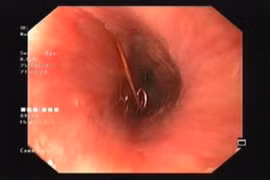

Các bác sĩ Bệnh viện Hữu nghị Việt Nam - Cuba Đồng Hới đã phối kết hợp, thực hiện thành công nội soi phế quản cấp cứu lấy dị vật dưới gây mê cho bệnh nhân 9 tuổi nuốt phải xương cá khi ăn cháo.